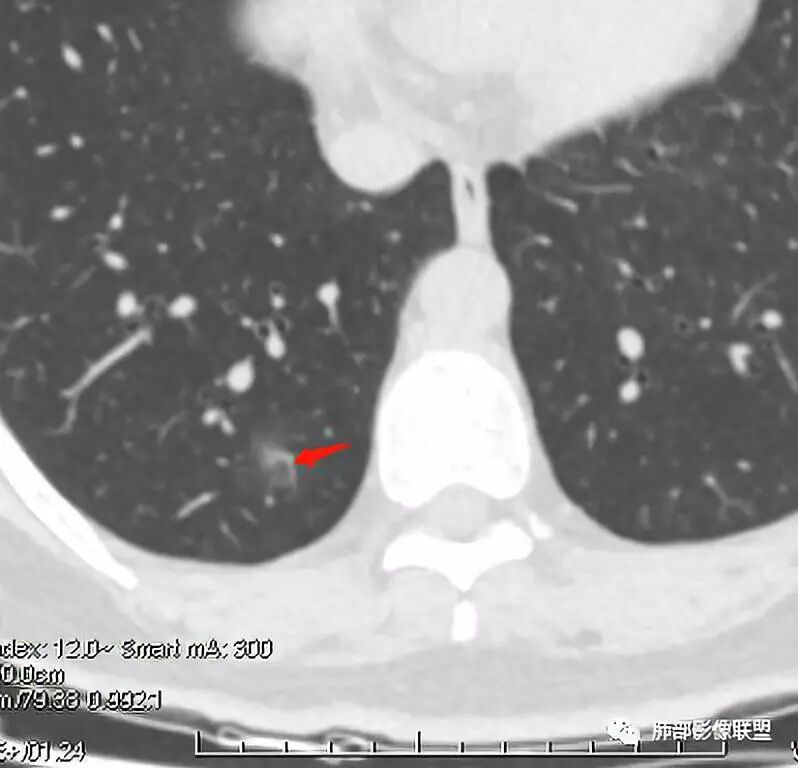

晨读:52f,体检发现右下肺结节,空洞、周围晕征(磨玻璃),局部血管影增粗,考虑1.真菌感染;2.GPA或不典型单发转移待排。

晨读:体检发现肺部结节,胸部CT:右下肺混合密度结节,结节中心空泡,壁光滑,结节边缘模糊,软毛刺,结节血管相对清楚,考虑良性结节可能,抗炎后复查。

右下肺混合磨玻璃结节,其内见空洞,空洞壁光滑,结节周围可见晕征,可见增粗血管,首次体检发现患者无症状,还是建议抗炎2周,1个月后复查,鉴别腺癌。

右肺下叶混合磨玻璃结节,边缘清晰,有分叶,毛刺,内见空泡。考虑腺癌。常规可以抗炎后复查。

体检发现肺部结节,右下肺混合密度结节,结节中心空泡,壁光滑,结节边缘模糊,血管在结节内增粗,矢状位前基底段还有一片磨玻璃影,所以考虑良性结节可能,炎性肉芽肿?抗炎后复查。腺癌合并炎性改变待排。

晨读病例,右肺下叶小结节病灶,内可见光滑空洞,周围可见边缘模糊磨玻璃影,首先考虑感染性病变,真菌或结核可能,鉴别腺癌,后者小病灶空洞少见,周围磨玻璃影清晰,胸膜凹陷征。

病灶大部分磨玻璃边界是模糊的,但有些地方还是比较清楚,腺癌是不能完全排除的,建议1个月后复查。

mGGO,周围有晕,边界不清,空洞,收缩力不强,血管通过走形正常,首先考虑炎性结节,抗炎和复查。筛查真菌。

内部低密度是空洞还是扩张的细支气管有疑问,边缘有的层面清楚有的层面模糊,恶性待排吧。

右肺下叶混合磨玻璃结节,边缘清晰,有分叶,毛刺,内见空泡。考虑腺癌。

我未见过的类型,CT征像良恶参半。女性,52岁,腺癌的好发人群。良性征像外周纯磨玻璃影很大,而且境界欠清晰。恶性征像,中央薄壁气囊边缘实性增厚,而而且厚薄不均匀。结合性别年龄,腺癌首先考虑,处理:随访3-6月,看看实性部分有无增多,应该不影响生存率。

磨玻璃结节,中央有空洞,周围晕征,磨玻璃血运明显,考虑腺癌,鉴别隐球菌。

晨读:结节伴晕,晕模糊,内有小空洞,周边还有片状模糊影,支持首先考虑炎性,临床会先抗感染治疗后复查。

晨读:右下肺结节,结节中心小空洞,壁光滑,结节周围有晕,边缘模糊,其他基底段亦可见斑片磨玻璃影,考虑炎性肉芽肿。隐球?寄生虫?

晨读:中老年女性,体检来诊。右肺下叶后基底段近胸膜下mGGN,其内实性成分似见毛刺及分叶,并见空泡征,周围GGO边界清楚,近肺门端见血管影伸入病灶并略显扩张,病变与支气管关系观察欠佳。多考虑恶性,腺癌可能性大。鉴于首次检查,常规建议抗炎治疗后复查,观察病灶变化情况,再决定下一步诊疗方向。

晨读,中老年女性,右下肺混合磨玻璃结节,边界模糊,内有空泡,张力高,考虑支气管扩张,周围血管相连,稍有增粗,考虑良性病变,细支气管扩张畸形并周围炎。腺癌待排。

晨读,女,52岁体检发现结节,右肺下叶见磨玻璃样结节影,边缘见毛刺,病灶内可见小空泡影,考虑腺癌可能,待除外炎性病变。

病灶内低密度像扩张的支气管,整体被病灶包围,可以定为空泡,PC没有这么大的牵拉,曲霉的话病变范围太小,而且是体检发现。病灶周围磨玻璃似清非清,病灶下缘磨玻璃是明确清晰的,因此诊断倾向于粘液腺癌,比较心虚的地方是没有抗炎复查。

右肺下叶后基底段混合型磨玻璃结节,边缘见晕征,内见小空泡/空洞,其内壁光整,与支气管关系不密切,常规考虑炎性肉芽肿病变,结核/隐球菌可能,腺癌待排,建议抗炎1月后复查。

右下叶后基底段混合密度结节,边缘磨玻璃模糊,晕征,中心实性成分似有多个小结节融合,收缩力不明显,中心空泡样改变内缘光滑,考虑小空洞,综合考虑良性炎性结节,隐球可能,结核与曲霉待鉴别。抗炎后复查或穿刺活检。

右肺下叶混合磨玻璃结节,中心有小透光区,壁光整,磨玻璃边缘模糊,收缩力不明显,考虑炎性结节,抗炎治疗后复查,代排隐球菌。

右肺下叶基底段胸膜下小结节,周围模糊晕征,其内光滑囊腔影,考虑小空洞,其内血管走形自然,周围软毛刺,常规考虑炎性结节,隐球可能性大,建议抗感染后复查,鉴别粘液腺癌。

从那么多天以来的读片结果看,不要走寻常路,各位老师考虑炎性的多,小隐球结节还是实性的多(见得少不知道对不对),空洞张力较高,那我考虑腺癌。